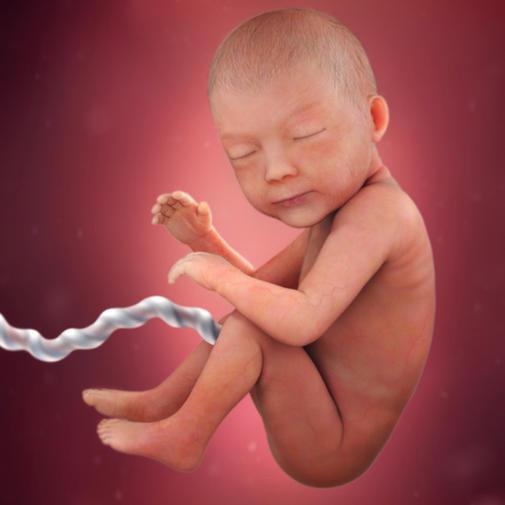

Ve 30. týdnu těhotenství měří plod zhruba 40 cm. Pro určení délky plodu se nyní používá součet délky hlavičky, trupu a nohou. Váha plodu je nyní zhruba 1300 g.